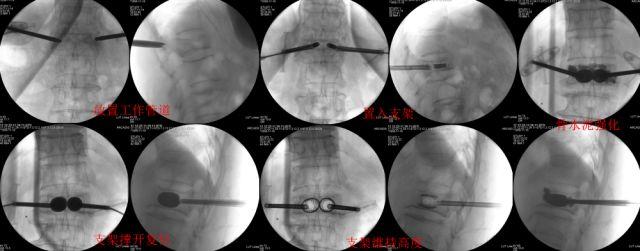

部分骨折程度较轻的患者,可以采取非手术治疗,以卧床休息为主,尽量减少下地活动,必要时佩戴支具;同时配合止痛药以及抗骨质疏松药物治疗等。而骨折程度较严重的或同时合并有高血压、糖尿病等内科疾病的患者,长期卧床反倒会引起压疮、心肺功能变差、驼背畸形甚至骨折压迫到脊髓造成截瘫等严重后果,这部分患者就要进行及早手术治疗了。大多数老人家可以采取微创手术治疗,“一针搞定”,切口只有0.7cm,术后第二天就可以佩戴支具或者腰围下床活动了。

施行手术时,病人不需全身麻醉,只需在局麻后,将骨针经背部的皮肤穿入骨折塌陷的椎体后,注入骨水泥,病人的疼痛可以很快得到缓解。一般治疗的时间大约在一小时内。待骨水泥硬化后,病人即可平躺,回到病房休息,一般手术第二天就可以佩戴支具下地活动了。这种手术成功率高,并发症低,安全有效。只要严格把握手术适应证,术中小心操作,微创手术能早期迅速地缓解腰背部疼痛,避免了长期卧床所致的种种并发症,提高患者的生活质量。

椎体成形术示意图

新型支架成形技术能很好的复位骨折椎体及维持复位后椎体高度。术中能预制空腔,有效减少术中骨水泥渗漏。另外金属支架与骨水泥很好的吻合,可能增加术后早期强化椎体的稳定性。